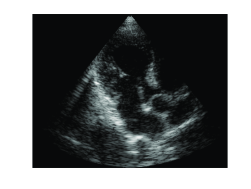

To demonstrate the proposed method, a subset μ𝜇\mu of 100100100 Fourier coefficients corresponding to the central frequency samples in the bandwidth of the transmitted pulse were chosen. To calculate μ𝜇\mu we need at most 133133133 samples per individual signal, implying 25 fold reduction in sampling rate. The result is shown in Fig. 5 (a). To compare the proposed solution with the previously developed OMP based method [6], the same subset μ𝜇\mu was used to reconstruct the beamformed signal assuming L=25𝐿25L=25 strong reflectors in each direction θ𝜃\theta. The resulting image is shown in Fig. 5 (b).

Refer to caption

(a)

(b)

Fig. 5: Cardiac images constructed from partial spectrum data with 25 fold reduction in sampling rate. (a) Modified l1subscriptl1\textit{l}_{1} optimization solution. (b) OMP based reconstruction.